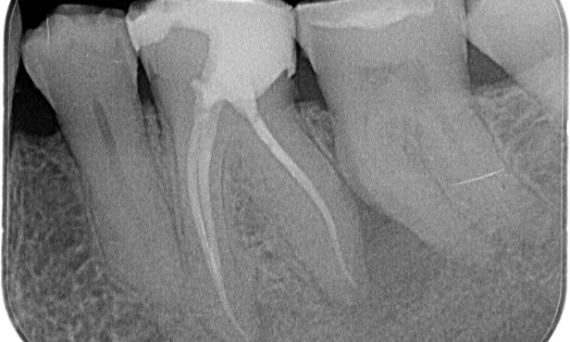

Después: En este caso, se eligió TruNatomy para permitir un enfoque apalancado en las caries y un enfoque en la conservación de la dentina pericervical, especialmente en el aspecto mesial donde el diente tuvo una restauración más mínima.

Después: La cavidad de acceso se realizó de la manera más conservadora posible. TruNatomy fue el sistema de elección debido a la edad del paciente joven. Necesitábamos preservar la dentina tanto como fuera posible para aumentar la capacidad del diente y así superar la carga oclusal y aumentar la longevidad de la restauración final.